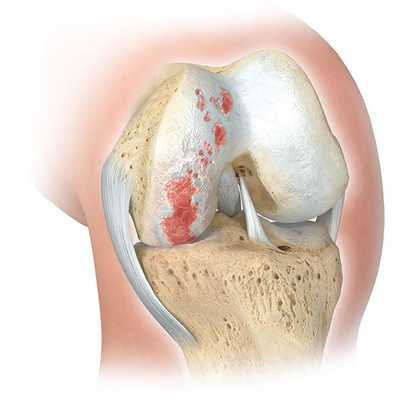

Артрит голеностопа на МРТ.

Чтобы выяснить причину воспаления, проводят лабораторные и иммунологические исследования. Для каждого вида артрита характерны свои изменения в анализах крови и синовиальной жидкости. При остром гнойном воспалении выявляют экссудат в синовиальной полости и нейтрофильный лейкоцитоз в крови. А при ревматоидном артрите обнаруживают высокие уровни ревматоидного фактора и АЦЦП.

Для определения стадии заболевания используют визуализирующие инструментальные методы. При острых и начальных стадиях хронических артритов информативны только УЗИ и МРТ. С их помощью можно обнаружить практически любые изменения в суставах и околосуставных тканях. На поздних стадиях, когда происходит массивное разрушение костей, достаточно информативна и рентгенография. Она позволяет обнаружить характерные для артроза изменения: сужение суставной щели, остеофиты, субхондральный остеонекроз, признаки остеопороза и т.д. При остром артрите рентгенография может выявить неравномерное сужение суставной щели, которое косвенно указывает на скопление гноя.